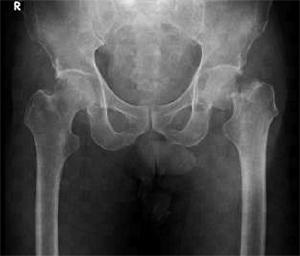

75歳の男性。転倒した後の股関節エックス線写真正面像を示す。骨折部位はどれか。

1

臼蓋部

2

大腿骨頸部

3

大腿骨転子部

4

大腿骨転子下

5

大腿骨顆部